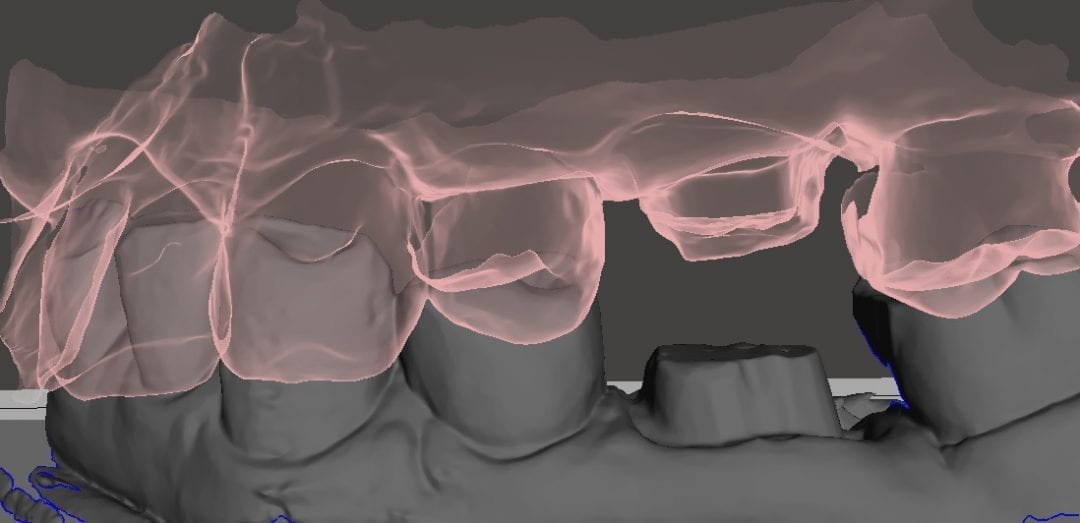

Image of case exported as STL